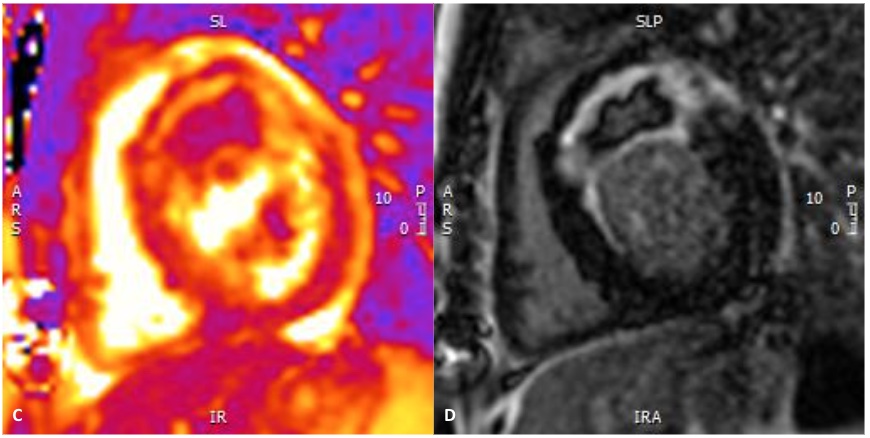

Figure 2. CMR performed eight weeks after the acute event. (C) T2 mapping, short-axis basal slice. (D) Late gadolinium enhancement (PSIR), short-axis basal slice.